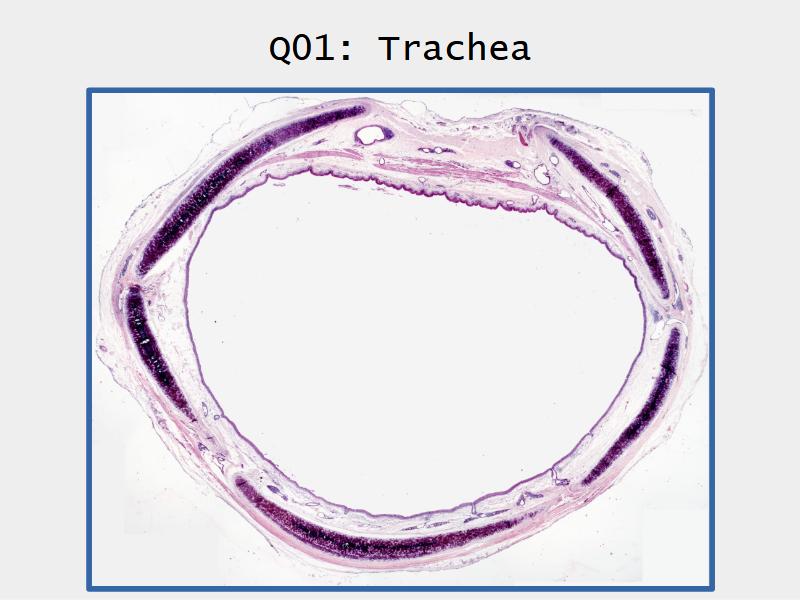

Slides: Respiratory System

- Slide 73: Trachea

Respiratory epithelium

- Pseudostratified

- Ciliated

- Columnar

- Epithelium with

- 4 Cells

- Ciliated columnar cells

- Non-ciliated columnar cells

- Goblet cells

- Basal cells

Trachea